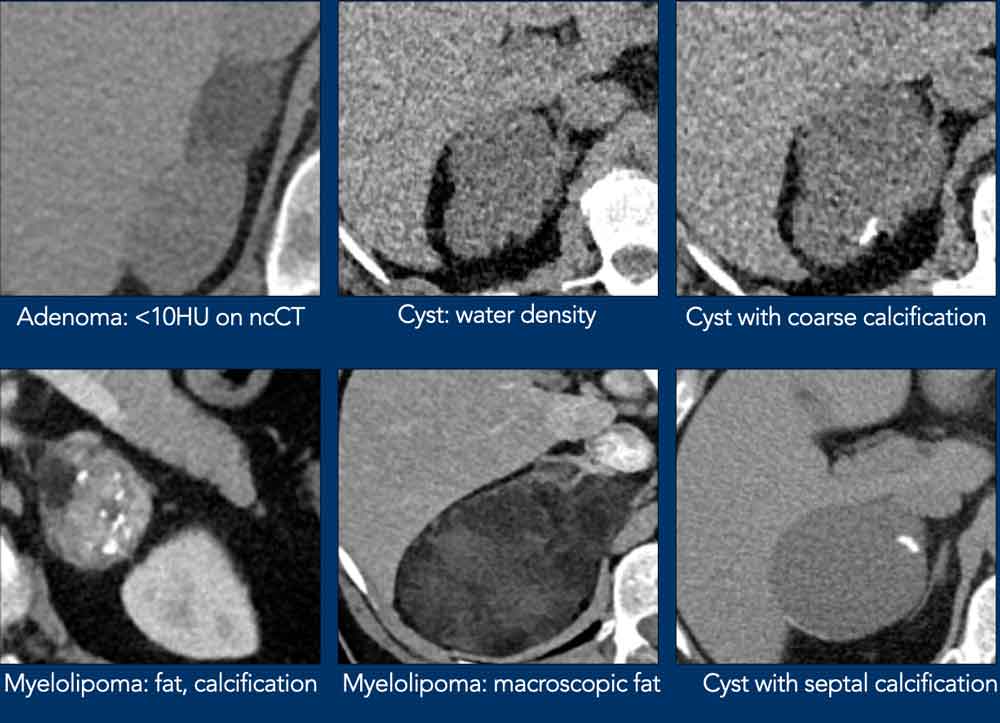

Typically Benign lesions

Many adrenal lesions can be categorized as typically benign and need no follow up (table):

- Lipid-rich adenoma

- Myelolipoma

- Cyst

- Hemorrhage (appriopriate history, e.g. trauma or severe illness)

- Lesions with benign calcifications

- Longterm ( > 6 -12 months) unchanged lesions (+ no history of cancer)

- Lesions that do not enhance

'No enhancement' is defined as less than 10HU difference between the unenhanced and enhanced CT.

Here some examples of typically benign lesions.

Lipid-rich adenoma

70% of adenomas contain high intracellular fat and will be of low attenuation on unenhanced CT [4,5].

A density equal to or below 10 HU is considered diagnostic of a lipid-rich adenomas.

Using a safe threshold value of 10HU on a native CT scan results in a sensitivity of 70-79% and a high specificity of 96-98% for the diagnosis of an adenoma [5-7].

Cyst

An uncomplicated cyst is a well-defined lesion of water density that does not enhance.

A cyst has a thin wall and may have thin septa.

It may be an endothelial cyst or a pseudocyst, which are the most common, or a true epithelial or parasitic cyst (both rare) [5].

Pseudocysts may have thicker walls.

Hemorrhage or debris may cause increased internal attenuation.

Both benign and malignant tumors may show cystic degeneration and necrosis.

In those cases density measurements are unreliable.

Features of an underlying tumor may be an irregular thick wall of 5 mm or more and mural, septal or solid enhancement [5].

Lesions with benign calcifications

Coarse rounded, peripheral or septal calcifications are typically benign and may be seen in:

- Adenoma

- Trauma

- Granulomatous infection

Bilateral calcifications also suggest a benign origin.

Myelolipoma

Myelolipomas are benign tumors composed of bone marrow elements.

Usually they are easy to recognize on CT or MR because they contain areas of macroscopic fat.

Calcifications are seen in 24% of cases.

The adrenal mass seen here on CT contains macroscopic fat, which is specific for the diagnosis myelolipoma.